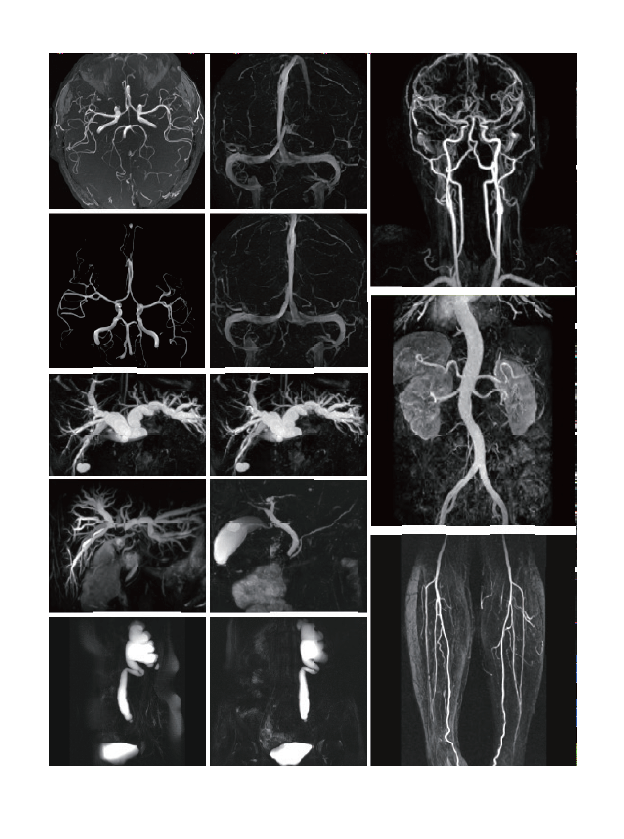

Comprehensive clinical applications

The examination range includes clinical applications such as nerves, blood vessels,abdomen, pelvic cavity, breast, tumor, orthopaedic limb joints, etc.

臨床畫廊